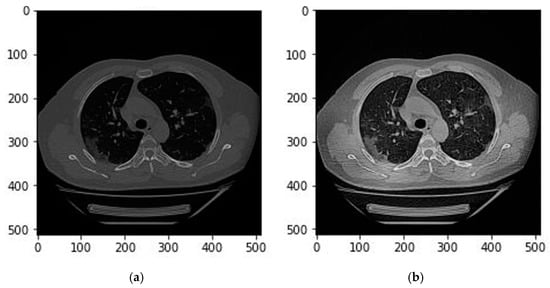

2.2. Image Preprocessing